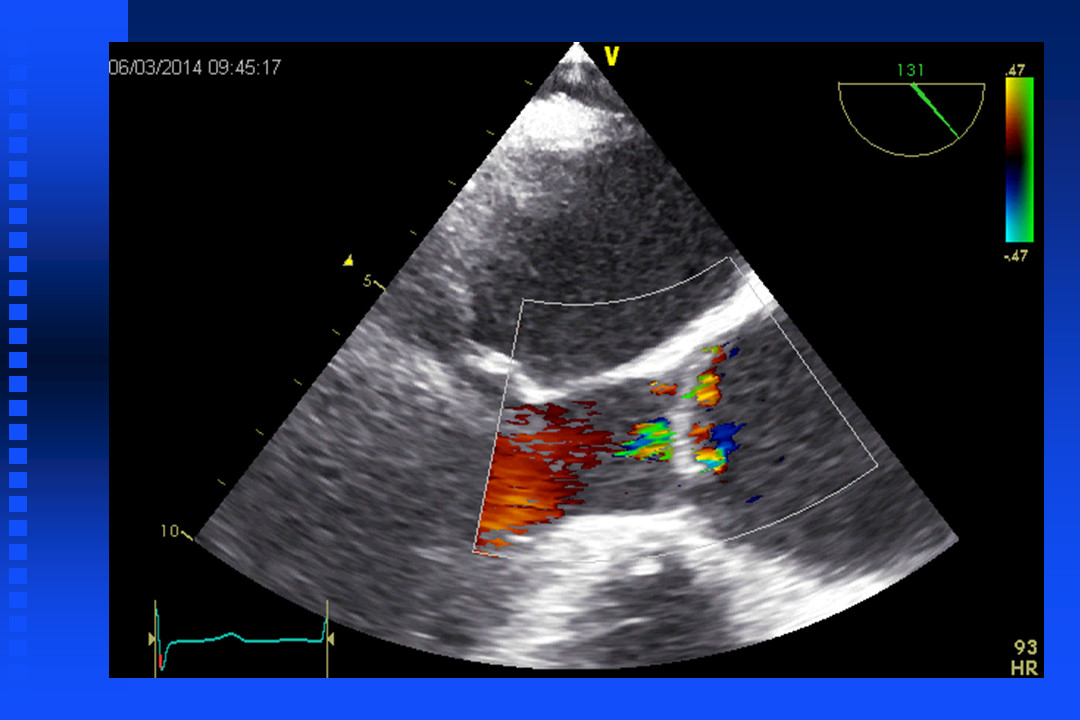

Short film mitral relaps

Short film mitral relaps with color doppler